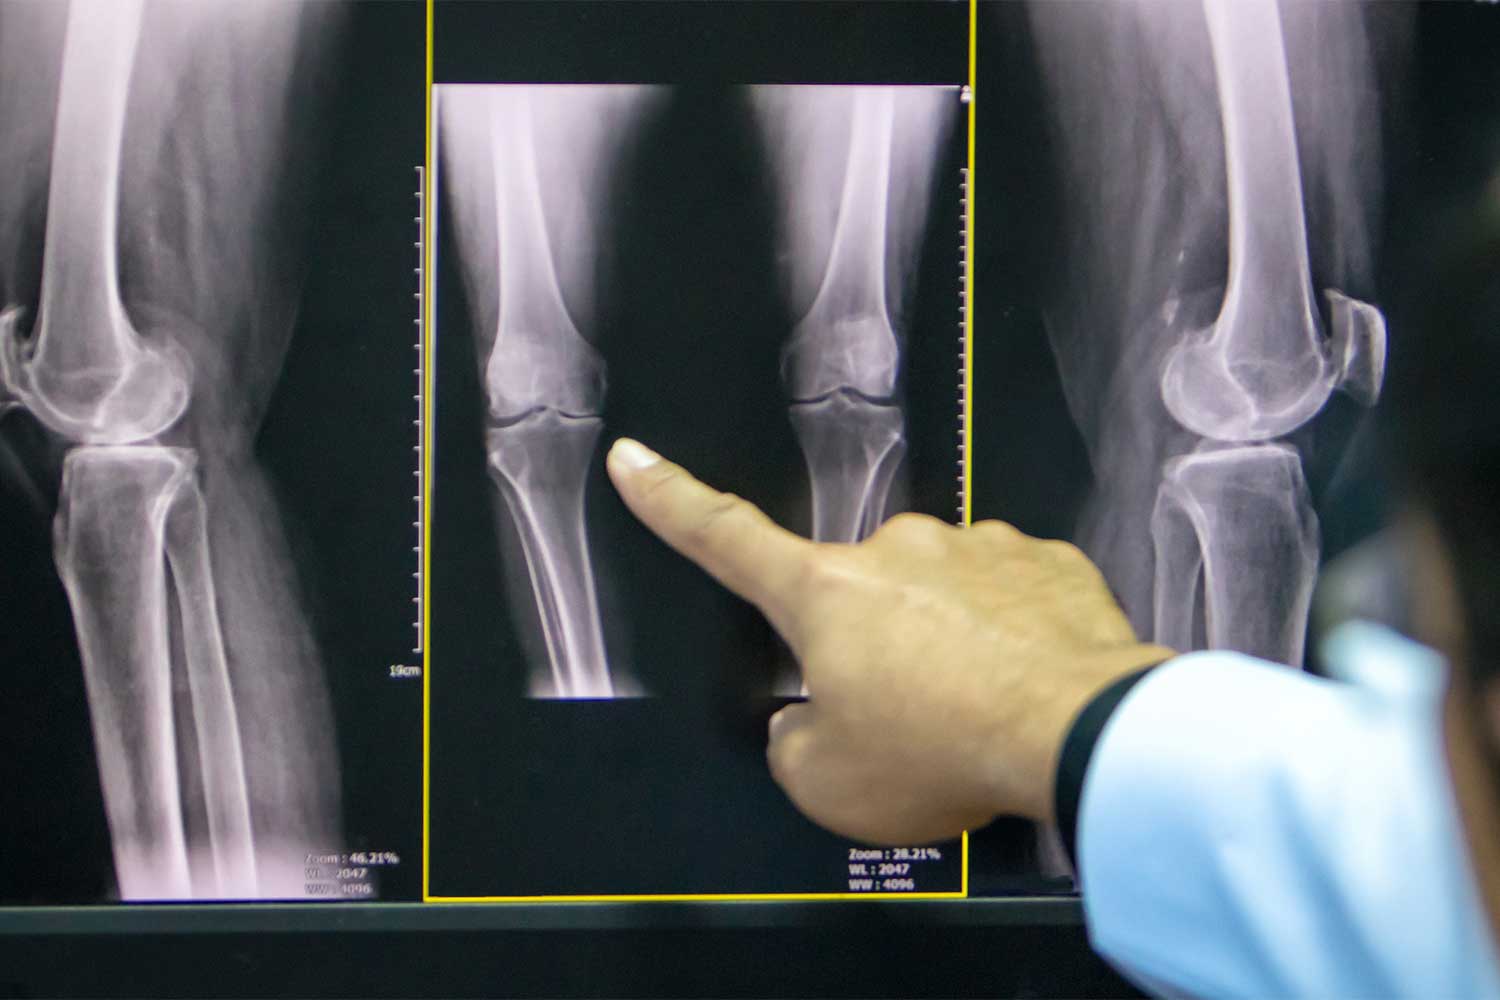

Медицинские снимки: рентген коленного сустава при остеопорозе